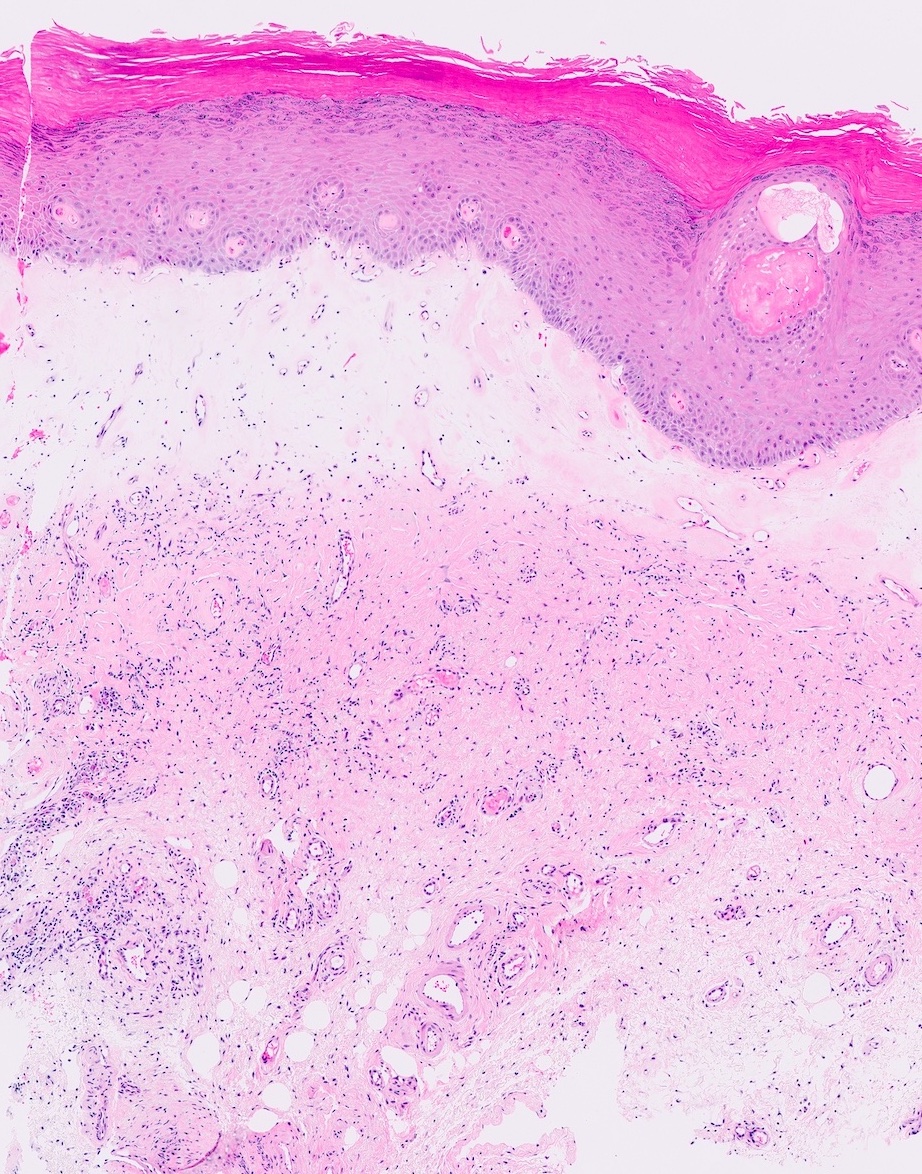

- Vacuolar interface reaction pattern in conjunction with dermal sclerosis (homogenized and hyalinized eosinophilic collagen bundles) of any thickness intervening between inflammatory infiltrate and epithelium or vessel walls (Mod Pathol 1998;11:844)

- Early lesions show only the inflammation and no or minimal fibrosis (inflammatory phase); the histopathological findings at this stage of disease development are not diagnostic

- Severe hyperkeratosis; thin epidermis, loss of rete pegs, basal cell degeneration, homogenized band of dense fibrosis at papillary dermis, upper dermal edema, band-like chronic inflammation

- In early stages, findings are subtle and often more prominent in adnexal structures than in interfollicular skin; adnexal structures show acanthosis, luminal hyperkeratosis and hypergranulosis

- Early dermal changes are homogenized collagen and wide ectatic capillaries in dermal papillae immediately beneath basement membrane

Microscopic (histologic) images